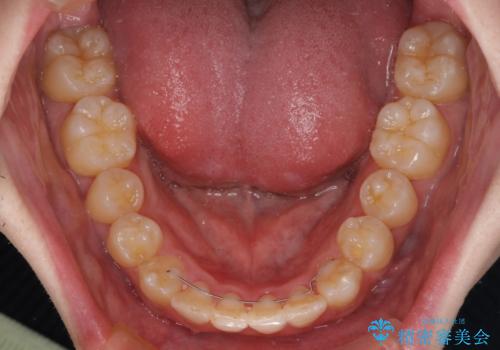

全顎的なクロスバイト 補助装置を用いてワイヤー矯正

- 八重歯や奥歯の噛みにくさを気にして来院された患者様です。

前歯のクロスバイトや八重歯の他に、左右最後臼歯のシザーズバイト(鋏状咬合)が認められました。

シザーズバイト改善のために補助装置を使用しながら、ワイヤー装置にて全体の歯列を整えることとしました。